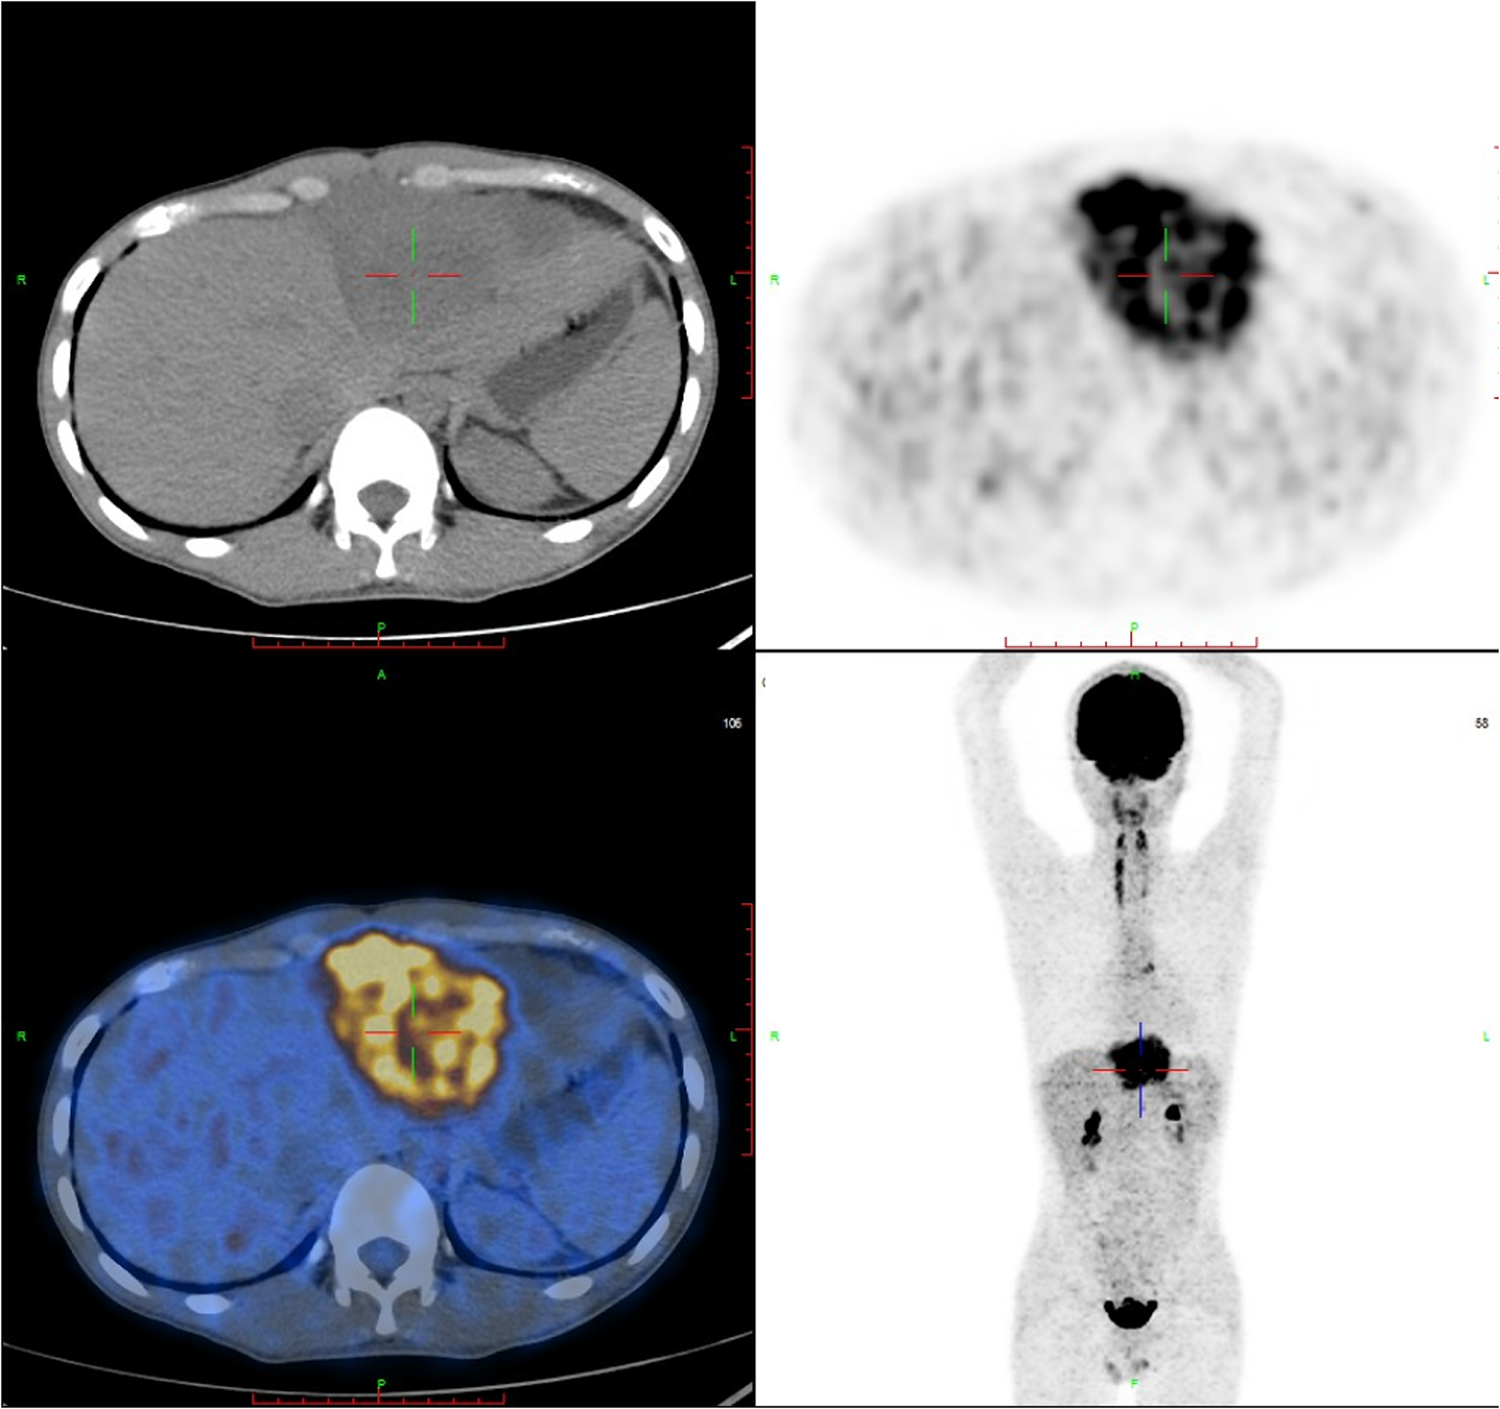

A F18-fluorodeoxy glucose-positron emission tomography (18F-FDG PET-CT) scan was recommended to provide additional information about the mass and evaluate its metabolic activity. The PET-CT scan revealed hypermetabolic activity located between the pericardium and diaphragm, with a standard uptake value (SUVmax) ranging from 5.4 to 15.9 (Figure 2). Additionally, hypermetabolic activity was detected in the lymph nodes of the right cardio-diaphragmatic angle, with SUVmax values of 5.9–7.3. No hypermetabolic lesions were detected in other parts of the body.

Figure 2. FDG-PET reveals hypermetabolic activity located between the pericardium and diaphragm, with a standard uptake value (SUVmax) ranging from 5.4–15.9, and no abnormal lesions are found in other parts of the body. FDG-PET, Fluorine-18 fluorodeoxyglucose positron emission tomography.